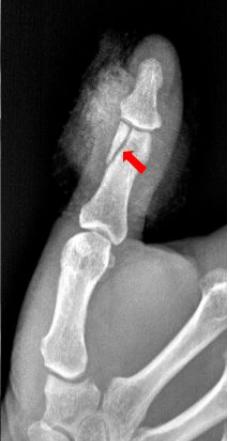

1、患者拇指被车门挤压,拍片如下:

右手拇指远节指骨甲粗隆游离骨碎片影

2、患者拇指被锤子砸伤,拍片如下:

右手拇指末节指骨见数条骨折线,骨折端对位对线尚可,右手拇指末节指骨粉碎性骨折。

3、患者拇指被车床挤压,拍片如下:

右手拇指近节远端见斜行骨折透亮线,断端稍分离移位,右手拇指近节远端骨折。